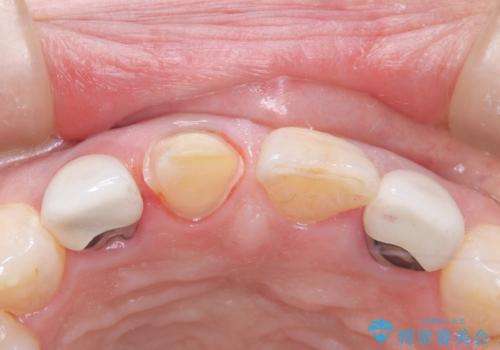

2日前に詰め物が取れ来院されました。中で虫歯が広がっている状態でした。歯科の治療が少し怖いとのことで静脈内鎮静を希望されました。

治療回数を減らしたかったため、虫歯をとり形成を行い仮歯への置き換えとともに型どりを行いました。